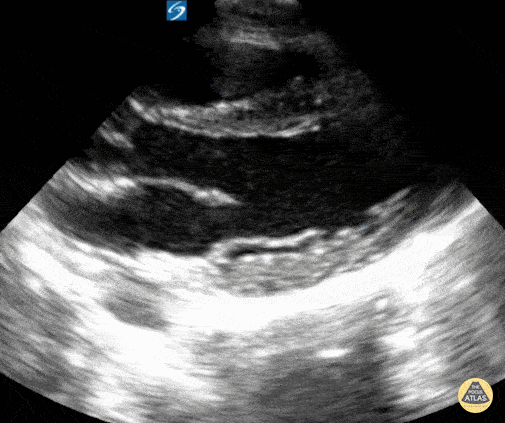

11 year old male presented to the emergency department with chest pain. Normal cardiac POCUS seen, and after a normal EKG and the chest pain resolved with ibuprofen the patient was discharged home. Contributor: Zach Boivin, MD, @ZachBoivinMD